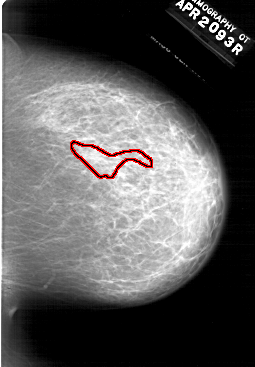

A_1696_1.LEFT_MLO

A_1696_1.RIGHT_MLO

A_1696_1.LEFT_CC

A_1696_1.RIGHT_CC

RIGHT_CC LINES 6226 PIXELS_PER_LINE 4321 BITS_PER_PIXEL 12 RESOLUTION 43.5 OVERLAY

RIGHT_MLO LINES 6406 PIXELS_PER_LINE 4891 BITS_PER_PIXEL 12 RESOLUTION 43.5 OVERLAY

FILE: A_1696_1.RIGHT_MLO.OVERLAY

TOTAL_ABNORMALITIES 1

ABNORMALITY 1

LESION_TYPE CALCIFICATION TYPE PLEOMORPHIC DISTRIBUTION SEGMENTAL

ASSESSMENT 4

SUBTLETY 2

PATHOLOGY MALIGNANT

TOTAL_OUTLINES 1

FILE: A_1696_1.RIGHT_CC.OVERLAY